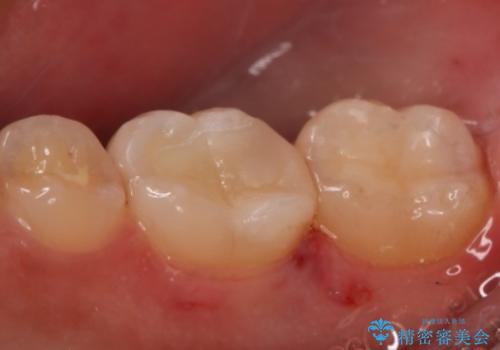

- 右下6・7番の治療のやり変えを主訴に来院された患者様です。

保険の材料が劣化し中で虫歯が進行しているため、古い材料と虫歯を全て除去した上で詰め直す必要がありました。

切削量・形態を考慮し、セラミックインレーでの治療を計画しました。

虫歯が深い場合、痛みなどの症状が出る可能性がありますが、経過は良好でご本人も満足されています。